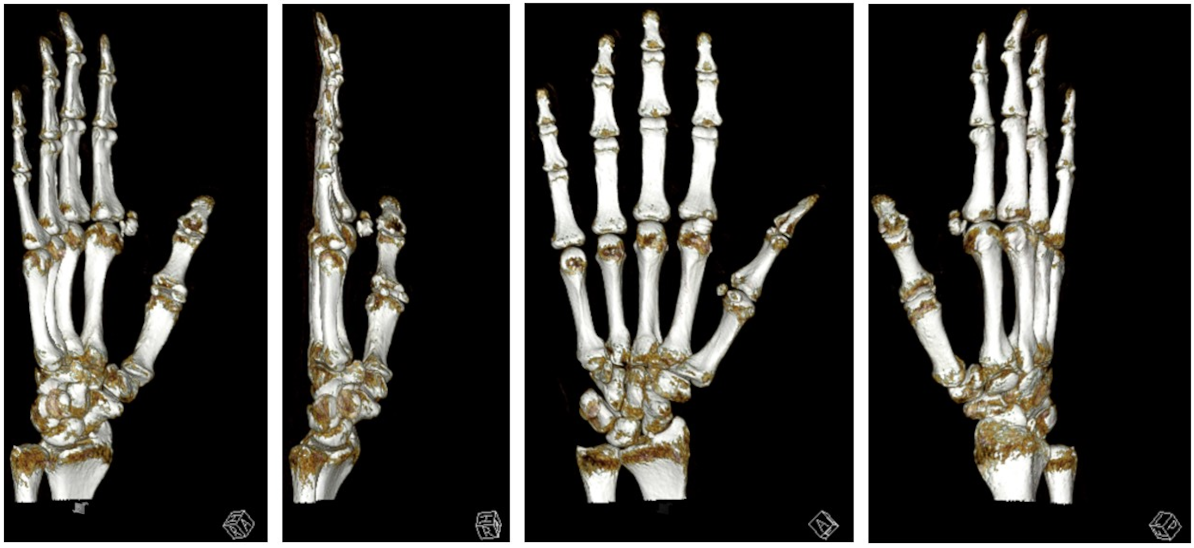

We performed a radiographic examination of the affected hand, followed by a contrast-enhanced CT scan. Based on the imaging findings, avascular necrosis of the sesamoid bone at the MCP joint was suspected (Figure 2 [Fig. 2], Figure 3 [Fig. 3] and Figure 4 [Fig. 4]).

Figure 4: 3D reconstruction of sesamoiditis

The procedure was performed one week after the initial diagnosis under plexus anesthesia (Figure 4 [Fig. 4] and Figure 5 [Fig. 5]). Upon obtaining intraoperative radiographs to plan the surgical approach, the sesamoid bone was no longer radiographically visible. Following the cutaneous incision, we encountered localized sepsis overlying the former sesamoid's location. The bone exhibited extensive osteolysis, with only residual osseous fragments remaining identifiable. A thorough surgical debridement was conducted, encompassing the complete excision of all infected and necrotic tissue (Figure 5 [Fig. 5]). This procedure included the removal of any residual sesamoid fragments, devitalized soft tissue, and purulent material to achieve a clean surgical bed and mitigate the risk of persistent infection. The incision-to-closure time was 84 minutes. Postoperatively, a firm dressing was applied until complete wound healing, and gradual weight-bearing was initiated after 14 days.